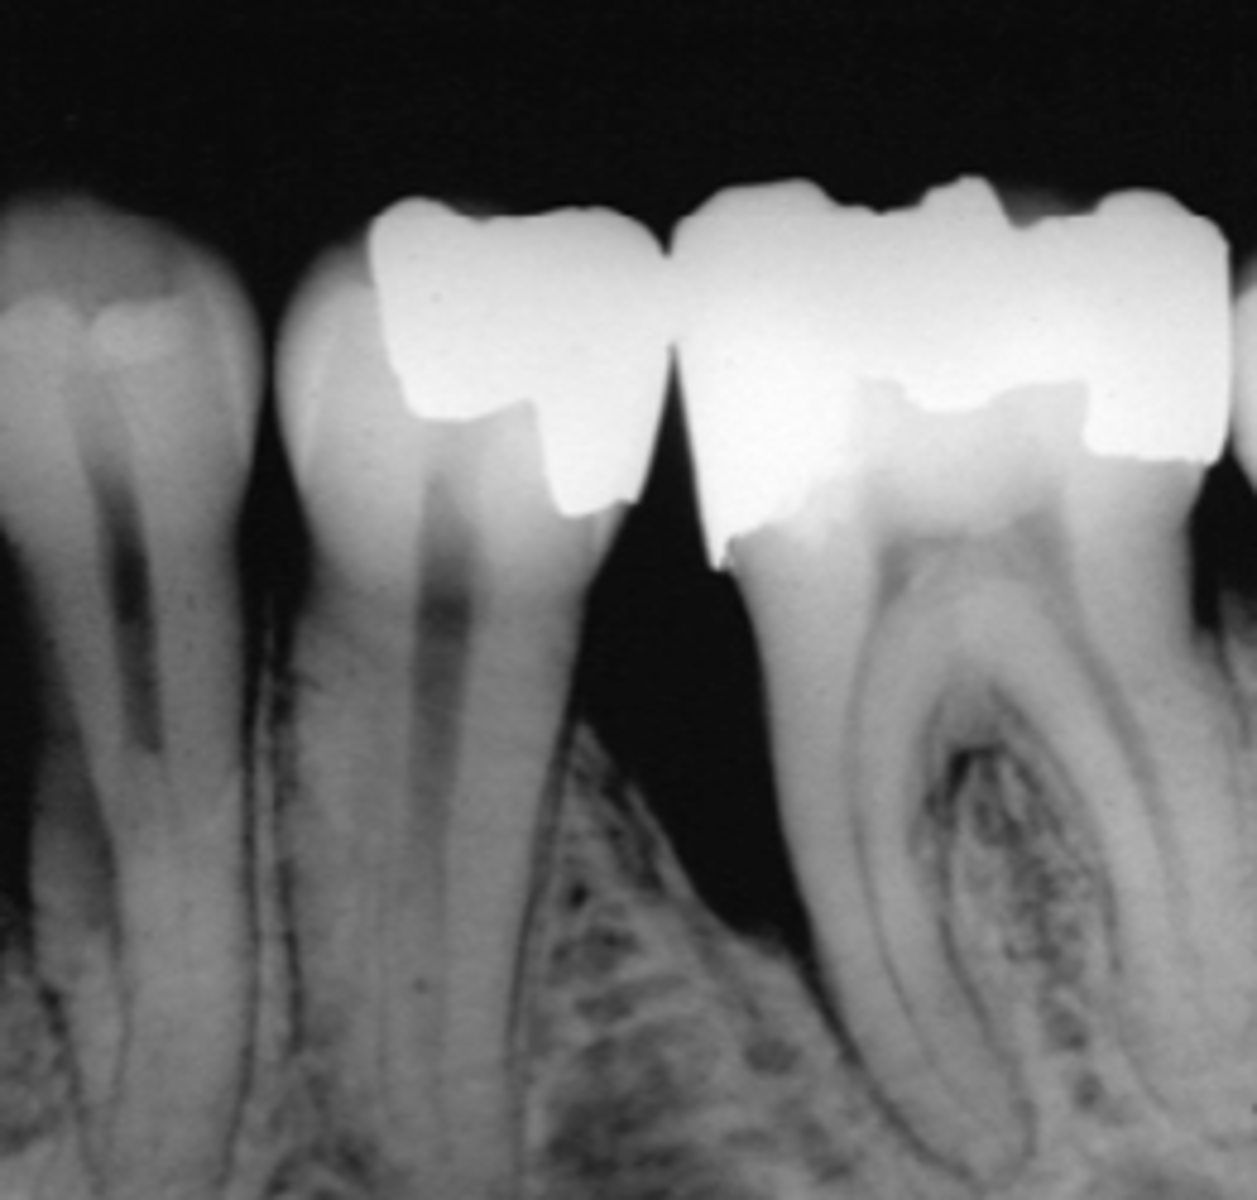

what are the different classications of caries

interproximal, occlusal, buccal and lingual, root surface, recurrent, and rampant caries

what are interproximal caries

caries between the teeth often at or below the contact point

what is a class I interproximal caries

extends less than halfway through enamel

what is class II interproximal caries

extends more than half way through the enamel

what is a class III interproximal caies

extends to or through the DEJ and into dentin

what is class IV inerproximal caries

extends through enamel and dentin more than half distance towards the pulp

what are recurrent caries

decay adjacent to an existing restoration

how can defective restorations affect periodontal disease

act as food traps and accumulate food debris and bacteria